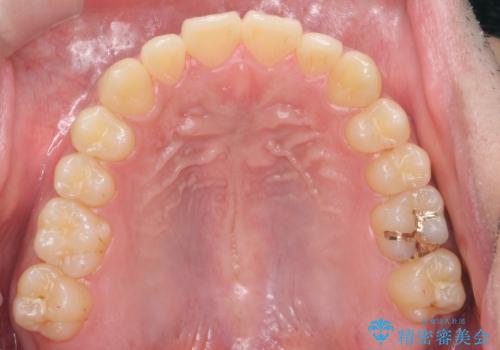

骨格性の受け口 非抜歯で下の歯を後ろに下げる インビザラインで インプラント矯正

治療により受け口が改善し、下あごの輪郭も若干後ろに下がった印象になりました。

当院では下の歯を後ろに下げるため矯正用ミニスクリューを用いてしっかり移動を行う等ご説明をし、治療開始しました。